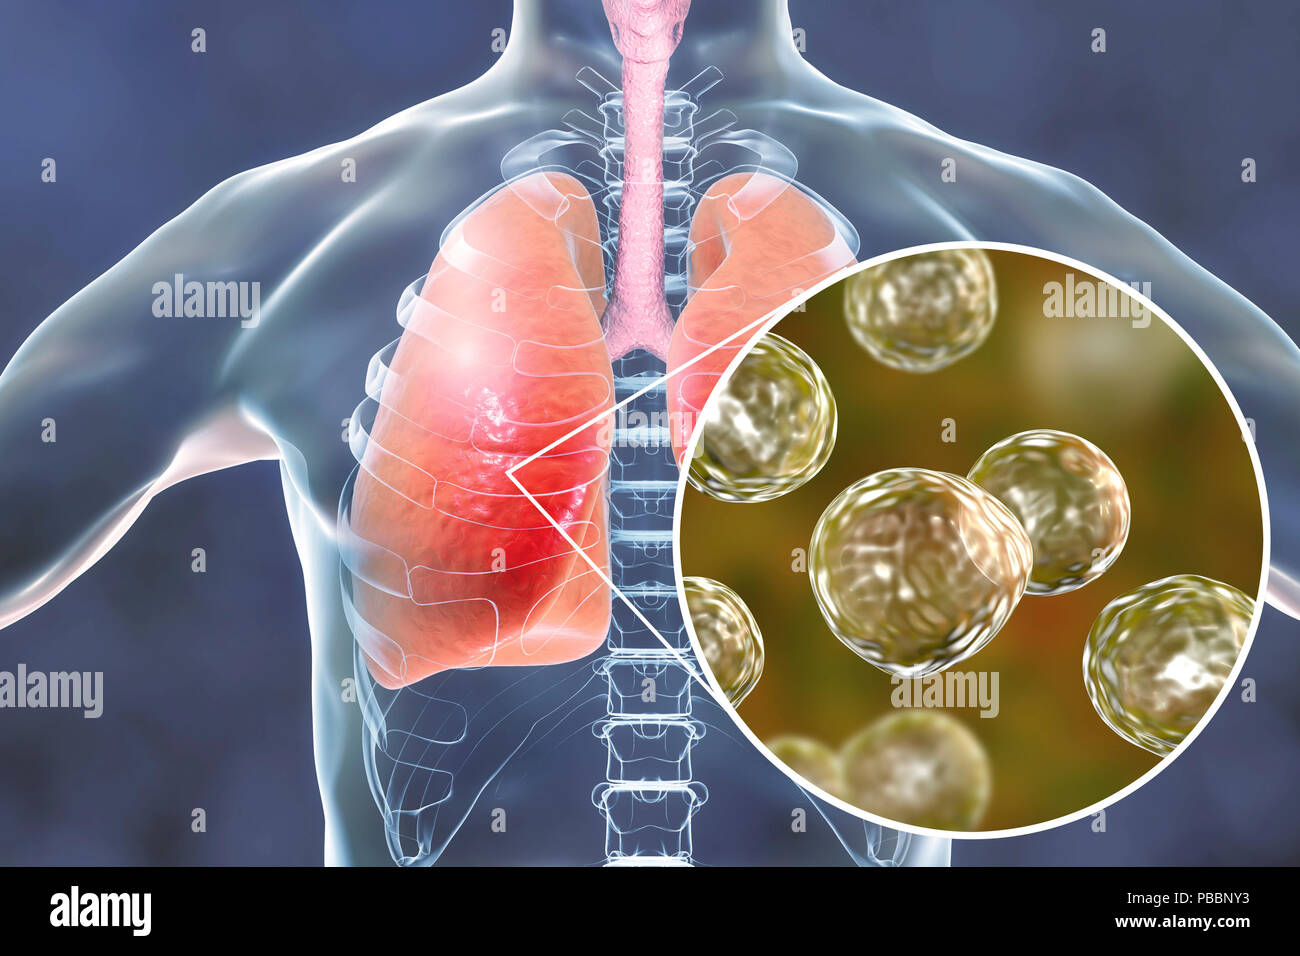

RFPBBNY0–La blastomycose pulmonaires, illustration conceptuelle. Blastomyces dermatitidis champignon est l'agent causal de la maladie de la blastomycose, qui dispose d'un éventail de présentations. Elle affecte principalement les poumons et peut causer une maladie semblable à la grippe, une maladie aiguë semblable à la pneumonie, une maladie chronique semblable à la tuberculose ou l'potentiellement fatals, le syndrome de détresse respiratoire aiguë. Dans certains cas, il peut s'étendre à la peau, des os ou des organes, causant des lésions. Le traitement est avec des médicaments antifongiques.

RFPBBNXX–La blastomycose pulmonaires, illustration conceptuelle. Blastomyces dermatitidis champignon est l'agent causal de la maladie de la blastomycose, qui dispose d'un éventail de présentations. Elle affecte principalement les poumons et peut causer une maladie semblable à la grippe, une maladie aiguë semblable à la pneumonie, une maladie chronique semblable à la tuberculose ou l'potentiellement fatals, le syndrome de détresse respiratoire aiguë. Dans certains cas, il peut s'étendre à la peau, des os ou des organes, causant des lésions. Le traitement est avec des médicaments antifongiques.

RFPBBNY3–La blastomycose pulmonaires, illustration conceptuelle. Blastomyces dermatitidis champignon est l'agent causal de la maladie de la blastomycose, qui dispose d'un éventail de présentations. Elle affecte principalement les poumons et peut causer une maladie semblable à la grippe, une maladie aiguë semblable à la pneumonie, une maladie chronique semblable à la tuberculose ou l'potentiellement fatals, le syndrome de détresse respiratoire aiguë. Dans certains cas, il peut s'étendre à la peau, des os ou des organes, causant des lésions. Le traitement est avec des médicaments antifongiques.